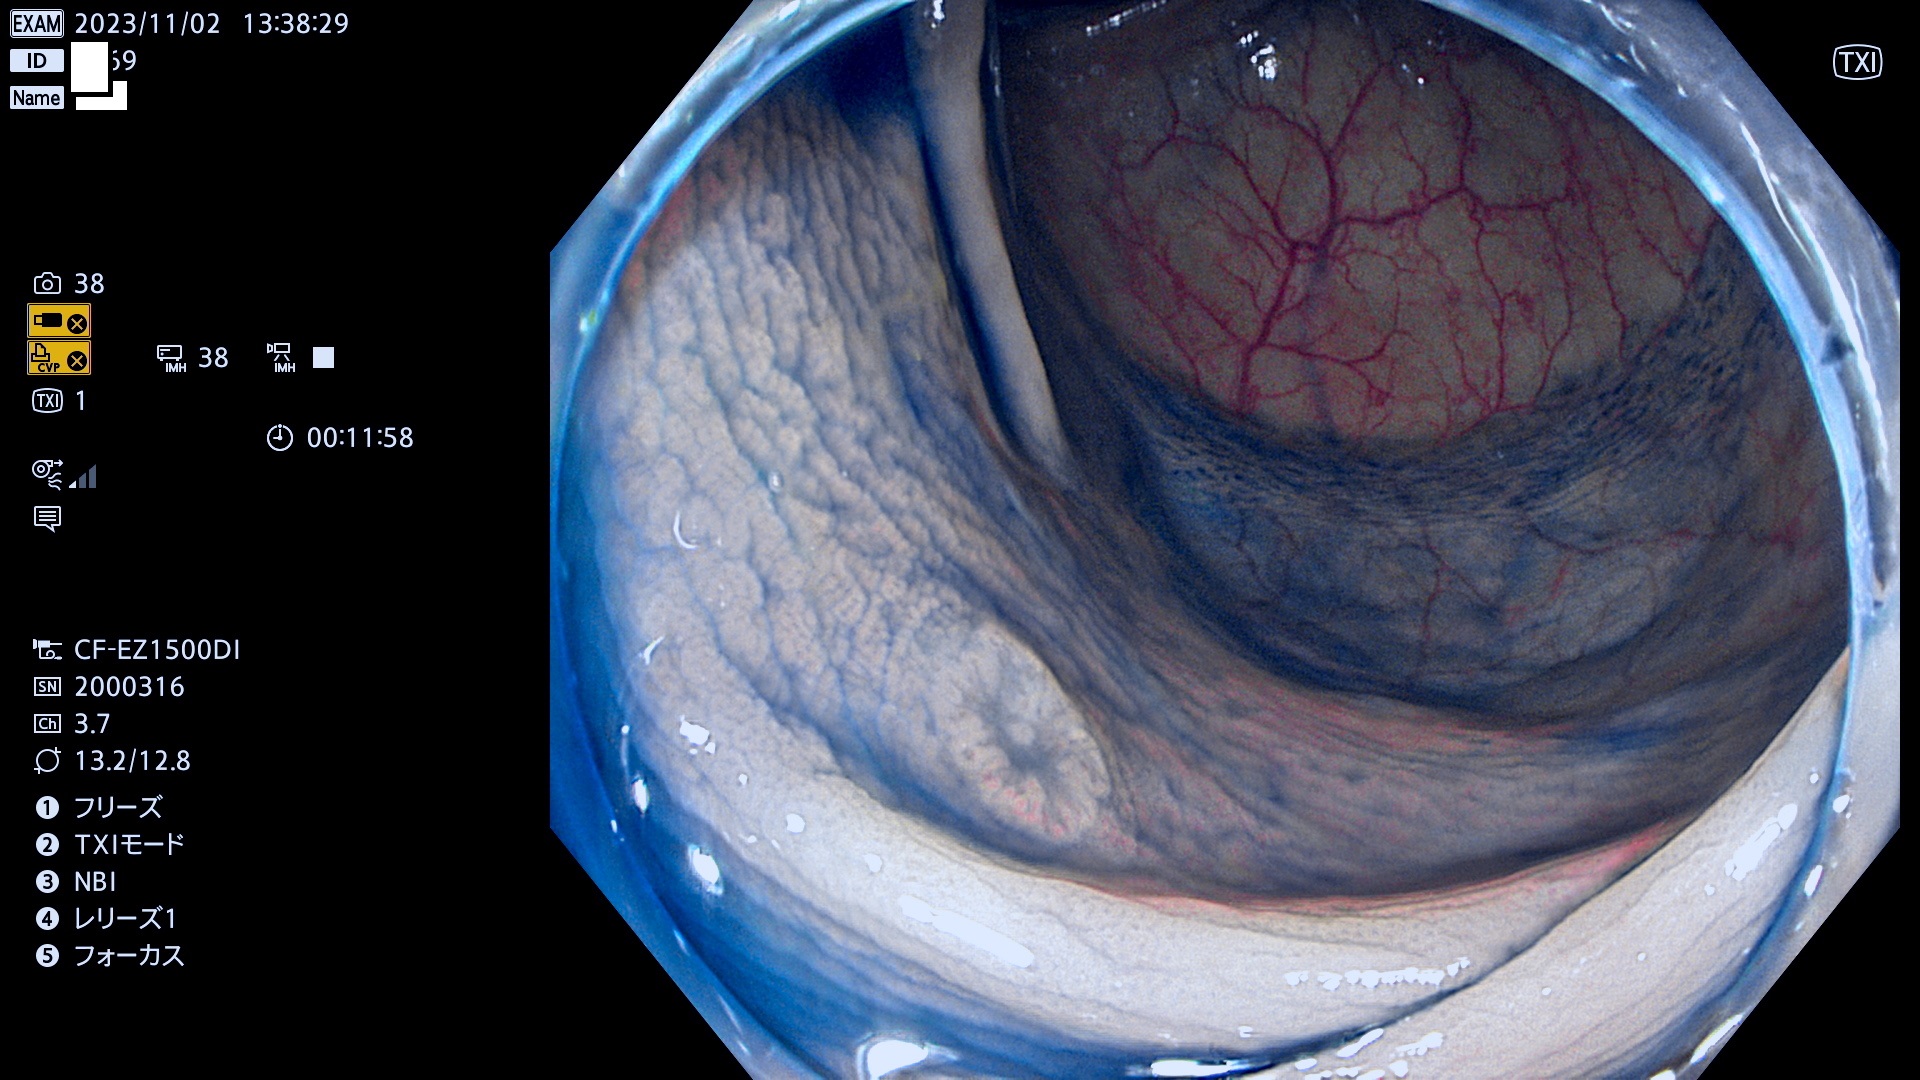

表面型腺腫(Flat Adenoma)の中で、完全に平坦な物をUb、陥凹している物をUcと呼びます。平坦隆起型(Ua)よりも、発見が難しく危険な病変です。このタイプは「内視鏡後・大腸癌の重要犯人」であり、この発見率は「腺腫発見率」よりも、重要な意味があります。

毎週の検査(木・金・土・日)に発見されたUb、Uc型・腺腫を、その週の日曜の夜にUPし1週間、提示します。

抽出の対象期間 2023年11月2日(木)〜11月6(月)の5日間(60件の検査)11件